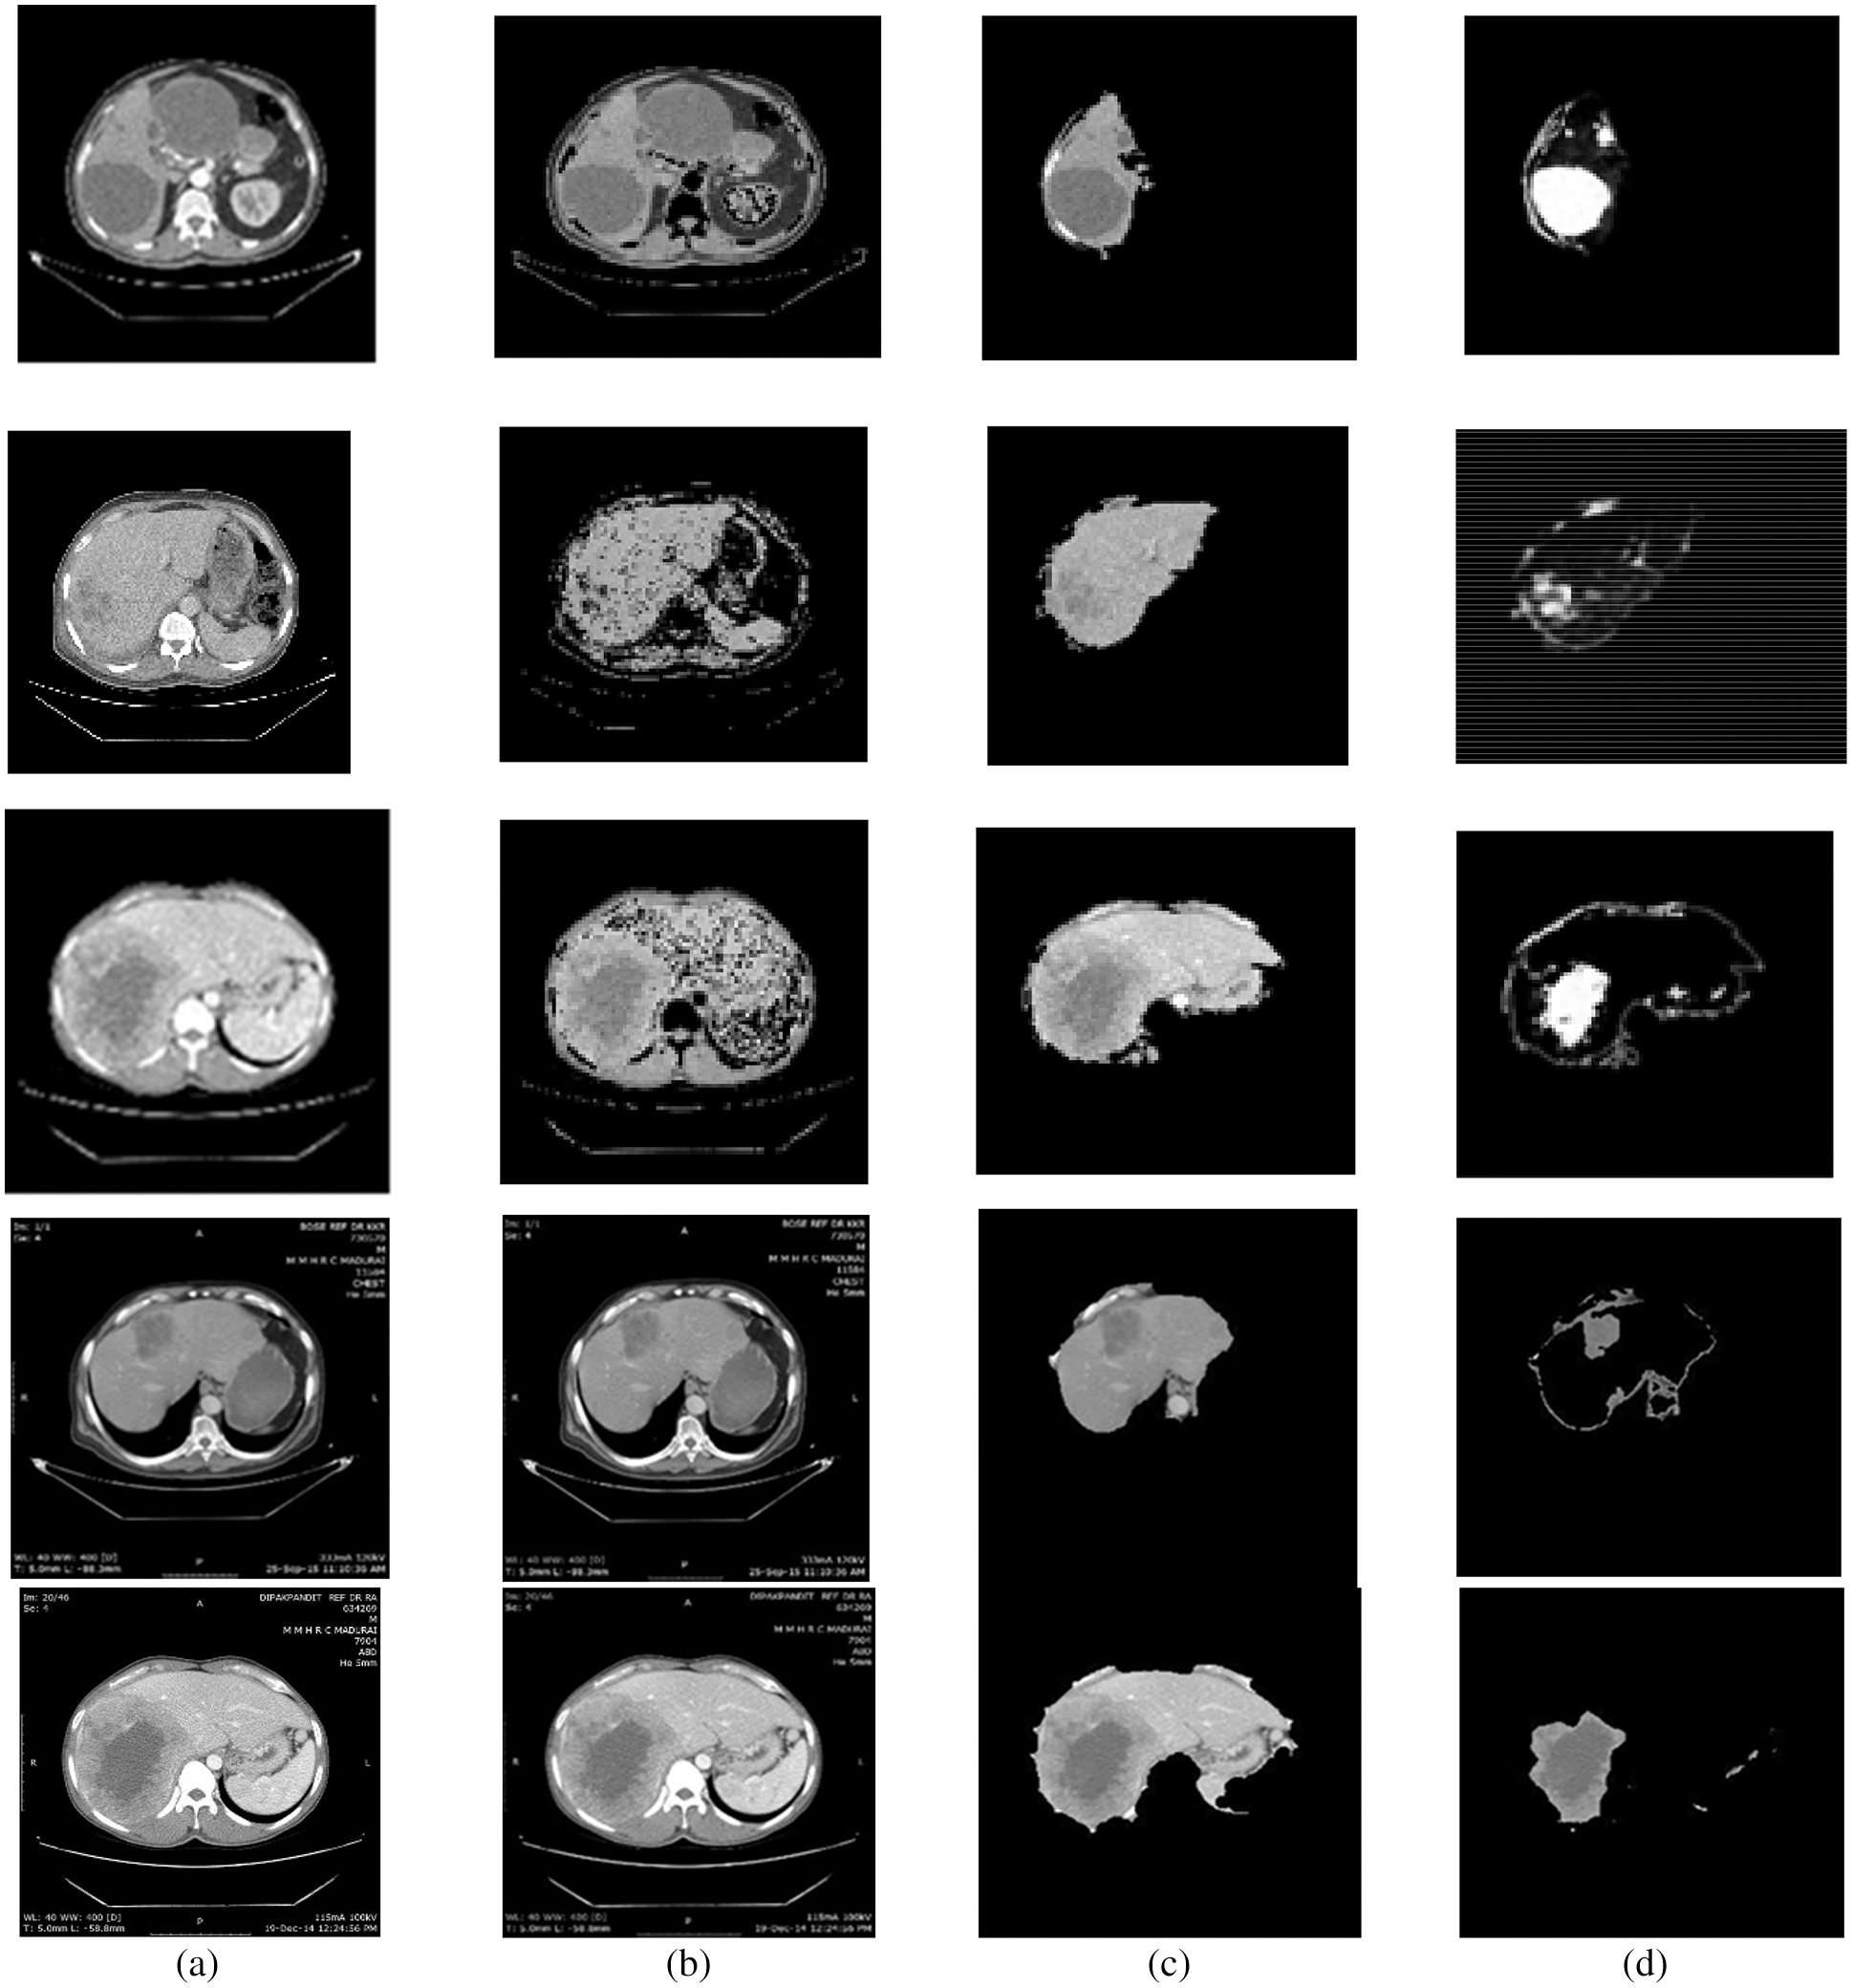

For this purpose, CE using NLMT is applied in this work. Figs. 2 and 3 show the proposed techniques’ segmentation results for the sample of 20 images in the public 3DIRCADB dataset (Figs. 4 and 5) (Tabs. 1 and 2).

Figure 3: Segmentation results of non-public dataset: (a) Input image, (b) processed output using CE using non-linear filtering, (c) output of AEM with CED algorithms, (d) output of MAT-ACM

Tab. 1, Figs. 2 and 3 show that the AEM with the Canny technique provides better performance results than the other existing traditional techniques. The mean VOE (6.92) and execution time (30 s) of AEM with Canny method is comparable with the existing methods (Li et al. 2013; Li et al. 2015 and Shi et al. 2016). Based on the qualitative, quantitative and comparative performance results, the most appropriate segmentation technique is identified, and its resultant image is considered for the following tumor segmentation process. The performance evaluation shows that the AEM with the Canny operator provides increased segmentation results for both empirical datasets.

The LTS is developed by implementing different FAS techniques. In experiments, the proposed and existing ST results are evaluated based on qualitative and quantitative analyses. Public 3DIRCADB and non-public datasets are used, and the resultant images from applying each ST are evaluated in the qualitative analysis. In the quantitative analysis, the performance of the techniques are analyzed using various performance measures. An AEM with a CED model is implemented, which increases the convergence speed of the iterative process for decreasing the Volumetric Overlap Error VOE (6.92%) values compared with the traditional techniques. The significant advantages of this technique are that it can detect the edges even in noisy environments and provide accurate positioning. So, the resultant image of AEM-CED is considered as the input for the LTS system. So, the MAT-ACM technique is implemented for accurate LTS. This technique follows the texture-based model, providing decreased VOE (3.08%) values than the existing methods and shows flexibility during segmentation.